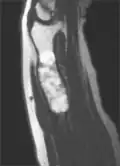

Magnetic resonance imaging (MRI), ultrasound, and scintigraphy are generally not practical for diagnostic purposes. X-rays are not as effective in the monitoring or evaluation of enchondromas due to frequent localized changes also sometimes due to the large number of enchondromas. MRI can sometimes however be used to monitor and evaluate symptomatic lesions in the case of potential malignant transformations.

MRI showing enchondromas localized in the lower part of the radius of a 37-year-old patient affected with Ollier disease -

MRI showing enchondromas localized in the lower part of the radius of a 37-year-old patient affected with Ollier disease. -